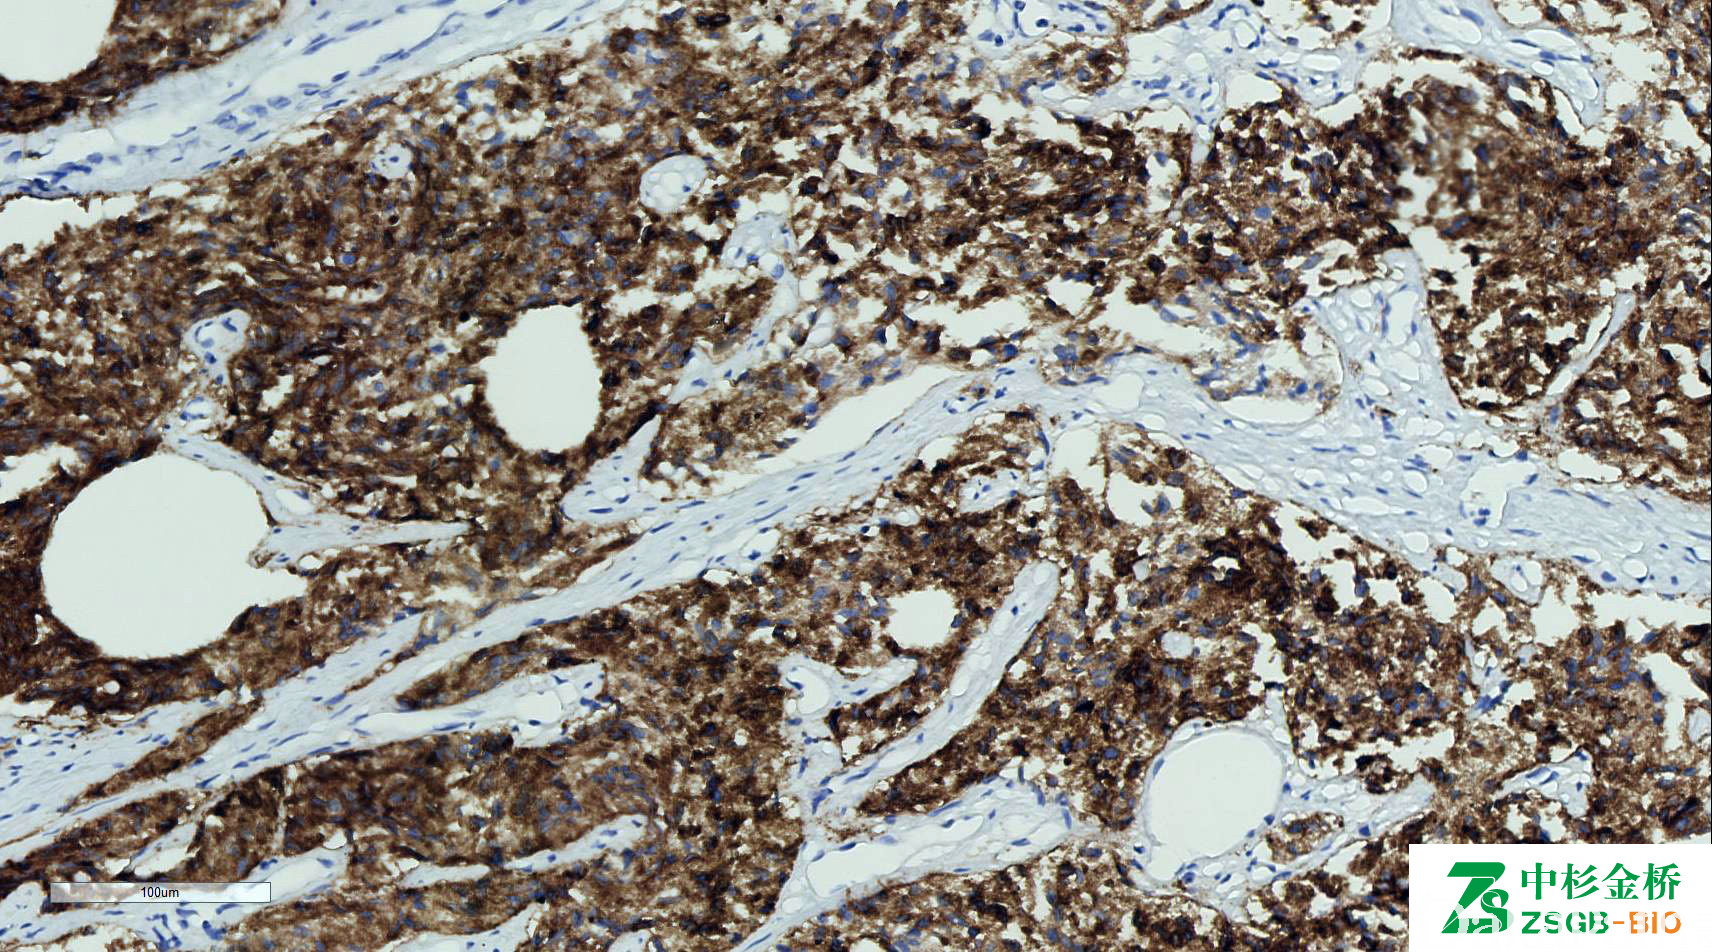

PSMA

在前列腺癌中表达,正常前列腺或前列腺增生中阴性或仅少量弱表达。

信号定位: 胞质、胞膜